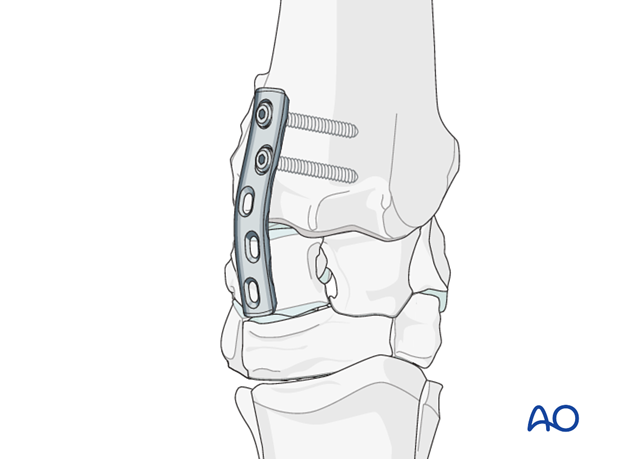

The plates are normally located craniomedially and craniolaterally over the intermediate and radial carpal bones of the proximal row. Occasionally, the plates will be placed over the intermediate and ulnar carpal bones if marked realignment of the limb is necessary.

For an antebrachial carpal joint arthrodesis, the medial plate is attached to the radius first and extended distally onto the radial carpal bones.

Once sufficient compression is achieved using the tension device in the first plate, the remaining screws are inserted into the radial carpal bones.